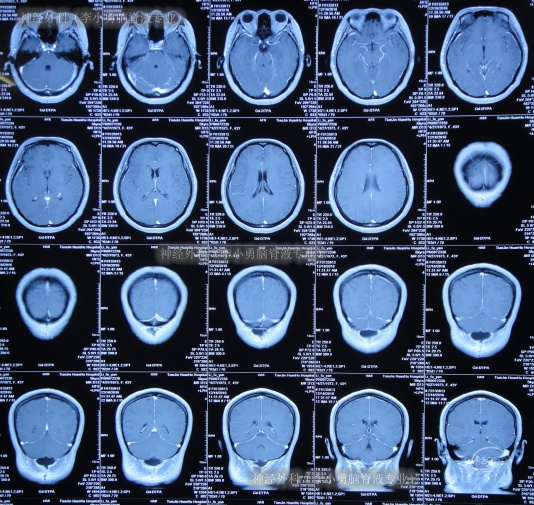

继续治疗1月余,头痛消失,期间3次查头颅CT(图-14)感染进一步变好。

图-14:期间3次查头颅CT

2017年3月7日(李小勇脑脊液专业住院57天)出院,出院时:头痛基本消失,体温变正常,皮下积液完全消失(图-15)。

图-15:2017年3月7日出院时

出院后3月半即2017年6月22日,来院复查,复查时:折磨患者间断10年余的头痛终于完全消失了,身体恢复至发病前健康的状态;查头颅CT示无异常(图-16)。

图-16:2017年6月22日

出院后2年零7月即2019年10月23日,来院复查,复查时:身体健康,每天开开心心,查头颅CT示无异常(图-17)。

图-17:2019年10月22日

出院后7年半即2024年9月20日,来院复查,复查时:在李小勇脑脊液专业治出院至今7年半身体各项一直挺好;查头颅CT示无异常(图-18)。

图-18:2024年9月20日